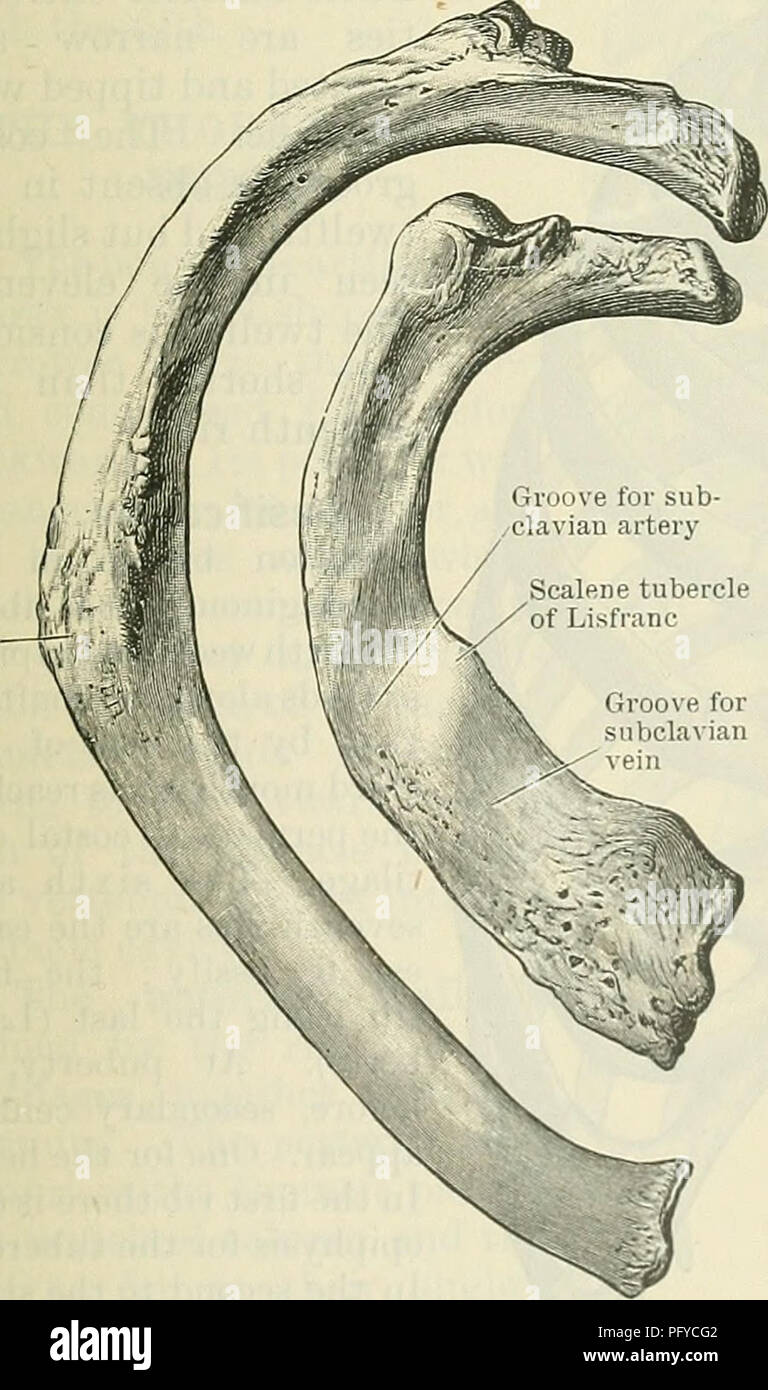

RMPFYCG2–. Cunningham il libro di testo di anatomia. Anatomia. Parte articolare del tubercolo per processi trasversali delle vertebre Fig. 124.-quinta costola destra come visto da dietro. attrezzatura per esterni ed interni dei muscoli intercostali rispettivamente. Sul pavimento della scanalatura può essere visto anche le aperture dei canali per la trasmissione delle navi di nutrienti che sono orientati verso la estremità vertebrale della nervatura. La sezione anteriore o estremità sternale dell'albero, spesso leggermente ingrandita, visualizza un ovale allungata buca in cui la cartilagine costale è affondato. Nervature peculiare.-Il primo, il secondo, decimo e undicesimo di

RMPFYCG4–. Cunningham il libro di testo di anatomia. Anatomia. Le nervature. Ill sfaccettature sulla testa Xeck Xon-articolare parte del tubercolo. Parte articolare del tubercolo per processi trasversali delle vertebre Fig. 124.-quinta costola destra come visto da dietro. attrezzatura per esterni ed interni dei muscoli intercostali rispettivamente. Sul pavimento della scanalatura può essere visto anche le aperture dei canali per la trasmissione delle navi di nutrienti che sono orientati verso la estremità vertebrale della nervatura. La sezione anteriore o estremità sternale dell'albero, spesso leggermente ingrandita, visualizza un ovale allungata abisso nel quale le carti costiera